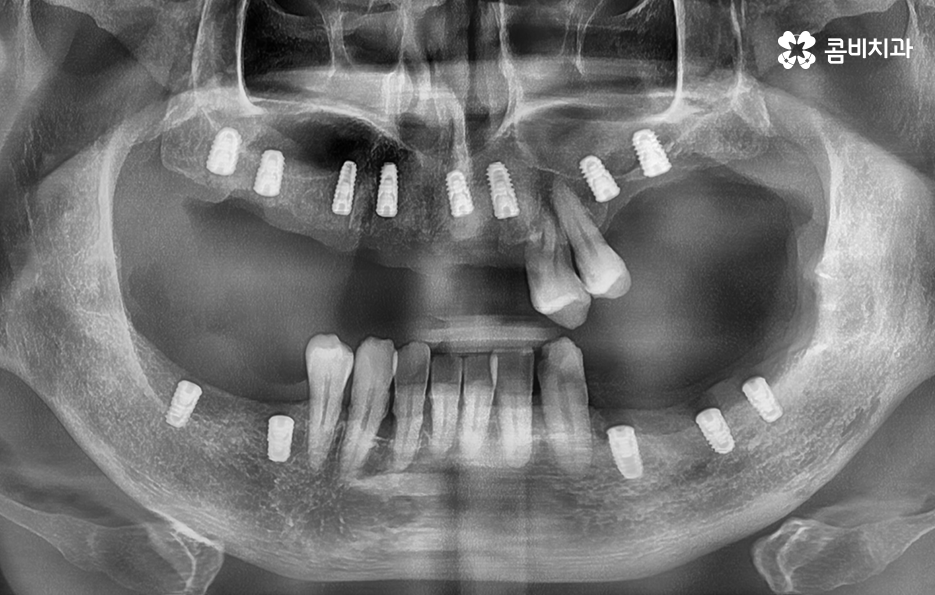

65세이상 임플란트 건강보험 혜택의 주된 내용은 65세이상 임플란트 개수 평생 2개까지 보험 적용 가능이라는 점으로 본인 부담률 30% 한하여 환자가 치료비를 부담하면 되기 때문에 경제적으로 상당히 큰 혜택이라고 할 수 있어요

다만 여기서 주의해야 할 점은 65세이상 임플란트 개수 평생 2개까지 혜택을 받을 수 있다는 점에서 되도록 자연치아의 건강을 잘 유지하면서 필요한 시점에 혜택을 잘 활용하는 것이 중요하겠고 노년기에 치료를 받아야 한다는 점에서는 잇몸 뼈의 상태 및 전신건강까지 잘 고려할 수 있는 시스템이 잘 갖춰지고 경험 많은 치과의사와 함께 치료 계획을 잘 세워야 하며 건강보험 혜택에서는 뼈이식이나 상악동거상술, 보철물의 변경 같은 추가적인 사항에 대해서는 별도의 비용으로서 치료비를 납부해야 하므로 각 환자분들에게 적합한 치료 계획에 대해 잘 이해하여 치료비 예산을 잘 계획하실 필요가 있었어요.

임플란트는 단순 치아 대체물이 아니고, 노년기 전신 건강과 영양 유지, 삶의 질을 지키는 치료로서 씹는 기능이 회복되면 식사량이 늘고, 영양 흡수가 좋아지고, 면역력도 안정되면서 전신 건강에도 긍정적인 변화가 생길 수 있기 때문에 치아의 상실에 대해 가볍게 여기지 마시고 기대수명을 고려한다면 60대는 물론이며 70대 혹은 그 이후에도 충분히 장기적인 관점으로 임플란트 치료를 바라보고 활용 및 관리하시길 바라고 있어요